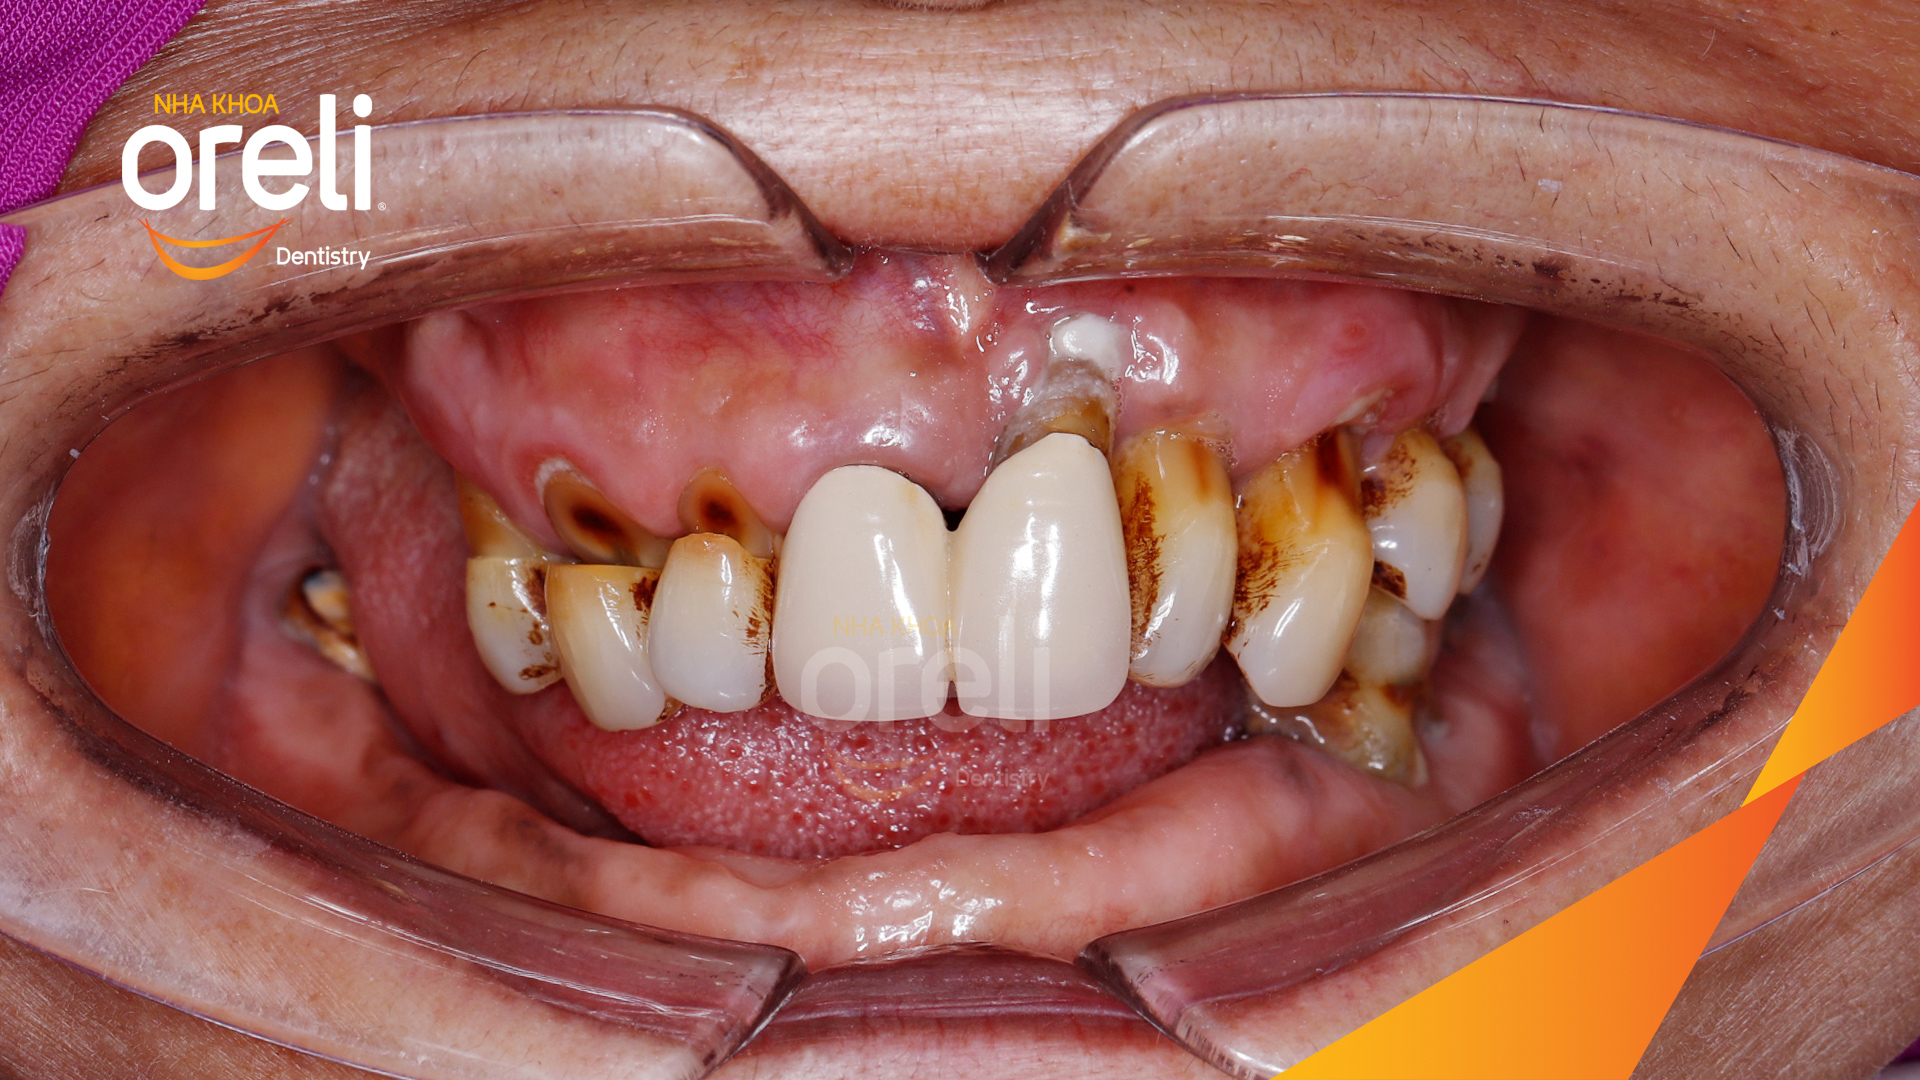

Tình trạng: Mất răng lâu ngày cả trên và dưới đặc biệt vùng răng sau

Giải pháp: Nhổ răng toàn bộ các răng còn lại do lung lay mất khả năng hồi phục

Hình ảnh thực tế